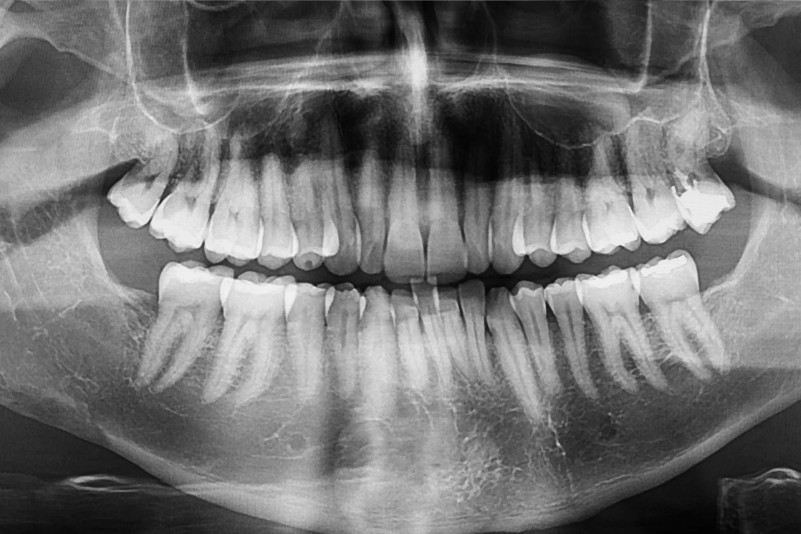

Estudios de imagen: radiografías y tomografía (CBCT)

Las radiografías panorámicas nos dan una visión general del estado de los huesos y los dientes, pero cuando necesitamos ver con más detalle, usamos la tomografía computarizada (CBCT). Esta tecnología nos permite ver en 3D cuánto hueso hay, en qué calidad está y si hay zonas donde necesitamos hacer regeneración. Es una herramienta clave para planificar tratamientos con injertos o implantes de forma segura y personalizada.

El diagnóstico suele incluir una radiografía panorámica y, si necesitamos más precisión, una tomografía 3D (CBCT). Esta última es clave porque nos permite medir el volumen de hueso disponible, identificar zonas debilitadas y planificar procedimientos como injertos, regeneración ósea o implantes. La tomografía también ayuda a detectar infecciones ocultas, quistes o pérdida ósea en áreas que no son visibles en una radiografía tradicional.